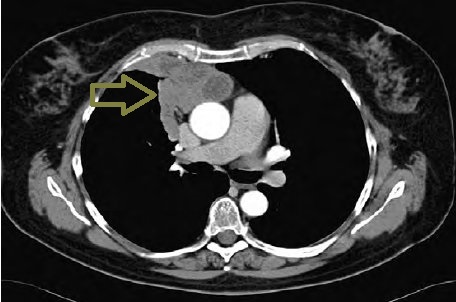

胸腺癌(悪性胸腺腫、浸潤性胸腺腫)

胸腺癌(悪性胸腺腫、浸潤性胸腺腫)は非常に稀で、標準的な治療が存在しません。組織型も、扁平上皮癌・未分化癌・小細胞癌と多様です。甲状腺機能亢進症/バセドウ病に合併した

- 胸腺癌(Thyroid Res. 2012 Jul 23;5(1):5.)

- 胸腺原発非定型的カルチノイド(Well differentiated neuroendocrine carcinoma、Atypical carcinoid)(第56回日本甲状腺学会 P1-085 メルカゾール投与後に蕁麻疹様血管炎を生じ、131I 治療の2年半後に胸腺原発異型カルチノイドと診断されたバセドウ病の1 例)

などが報告されています。

長崎甲状腺クリニック(大阪)では甲状腺機能低下症/橋本病に合併した胸腺癌(悪性胸腺腫、浸潤性胸腺腫)の自験例があります。

胸腺癌(悪性胸腺腫、浸潤性胸腺腫)は前胸部から肺門部まで浸潤し、横隔神経自体にも浸潤するため、摘出手術で横隔神経を損傷する可能性が高い(術後横隔神経麻痺)。術後横隔神経麻痺では、術後から息が深く吸えなくなります。内肋間筋・補助呼吸筋と代償性の呼吸数増加で補える場合が多いが、重症例は胸腔鏡下横隔膜縫縮術の適応。